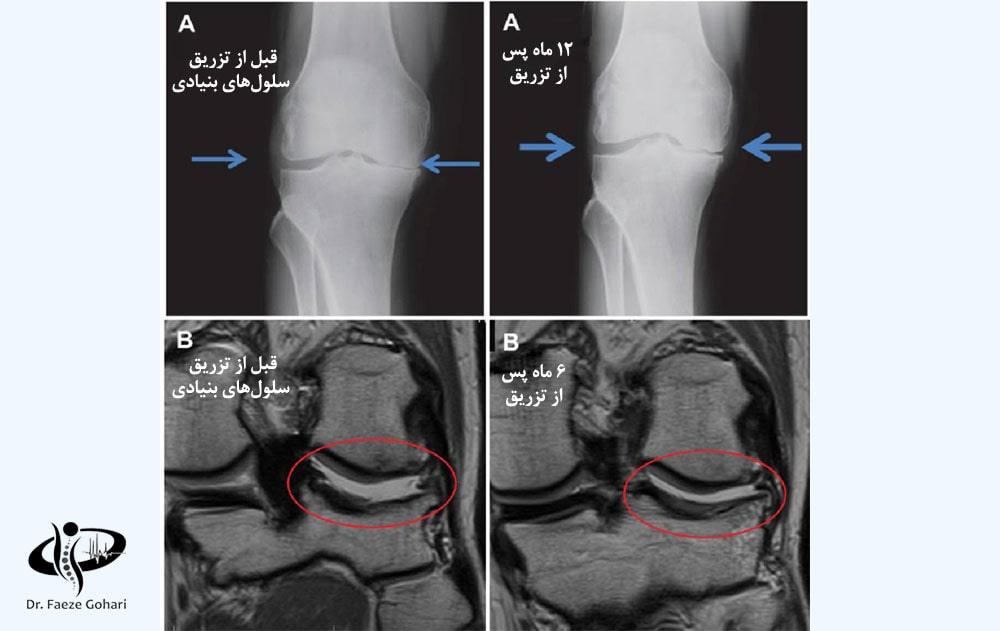

تصویر بالا مربوط به بیمار مبتلا به آرتروز زانو است که درمان با تزریق سلولهای بنیادی را دریافت کرده است. نتایج این درمان پس از ۶ ماه و ۱۲ ماه بهوضوح قابلمشاهده است. این نتایج شامل بازسازی غضروف، کاهش ساییدگی استخوانها، بهبود عملکرد مفصل و کاهش تورم و التهاب در ناحیه آسیبدیده است.